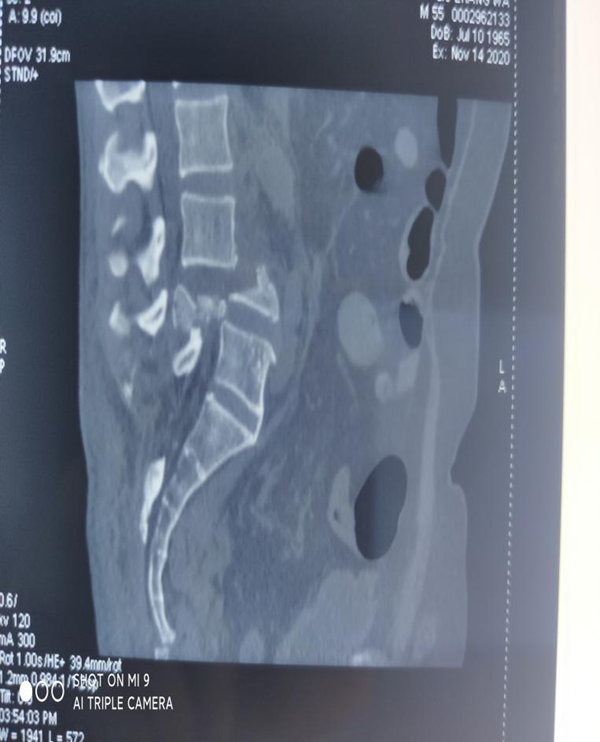

患者刘某,男,55岁,高处坠落致腰部疼痛伴双下肢麻木16小时主诉入院,由于腰部先着地,当时即觉腰部剧烈疼痛伴双下肢麻木和大小便失禁,伤后无昏迷抽搐,无腹痛腹胀,可回忆受伤时情况,伤后未作特殊处理,遂由家属送至我院急诊,查腰椎MRI:腰4椎体爆裂性骨折并继发椎体滑脱,为进一步治疗,急诊收住骨三科。

刘某家属找到了我院骨三科的张纯教授。张教授经过详细了解患者的病情,并判断这是一例严重复杂的脊髓损伤,需要立马进行手术治疗。于是为刘某联系了病房,结合患者年龄大、手术创伤大、出血风险高等特点,经过多次科室讨论及多科室疑难病例会诊,积极联合危重医学科、麻醉科、输血科等相关科室共同制定了周密的手术方案。根据患者病情制定了详细的手术计划及围手术期治疗方案。经过严密的手术前准备,以张纯主任医师为主刀、王伟卓主治医师和黄思华博士为助手,吴刚副主任医师、罗斌医师为麻醉医师,殷敏、马霞为配合护士,黄亚娟、王芳医师为术中诱发电位监护医师的手术团队努力下,手术顺利完成,切开复位内固定保护了严重受伤的脊髓,并进行了脊柱的重建。